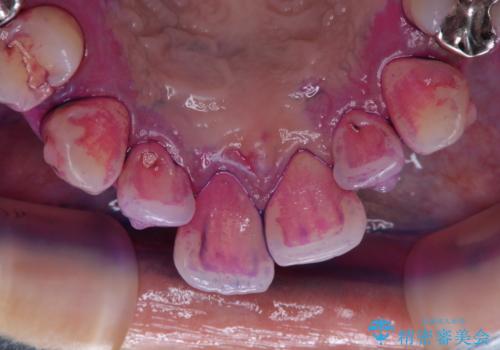

- インビザラインで矯正治療中にクリーニングを希望されました。PMTC60分コースで、クリーニングと歯ブラシ指導を行いました。

磨けているようでも、染出しをして目に見えるプラーク(歯垢)を確認することで、より正しいブラッシング方法を身につけることができます。インビザライン中は、歯にアタッチメントをつけるため、歯の表面がデコボコしてプラークが付きやすい状態になります。毎日のケアでしっかりと汚れを落として虫歯や歯周病・口臭のリスクを減らしていくことが大切です。定期的にメンテナンスを行い、ケアがどれくらい出来ているか確認したり歯科医院で専門的な機械や器具によるPMTCを行うことをおススメします。